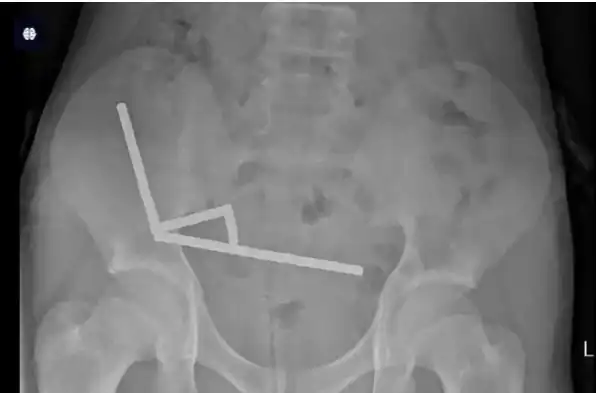

وأظهرت صور الأشعة وجود أربع سلاسل من المغناطيس مرتبطة ببعضها، يصل عددها إلى ما بين 80 و100 قطعة من مغناطيس النيوديميوم القوي، بقياس 5×2 مليمتر، اشتراها الطفل من موقع إلكتروني.

وأظهرت صور الأشعة التي نشرتها المجلة، أن المغناطيسات كانت موزعة في أجزاء مختلفة من الأمعاء، لكنها بقيت متصلة بفعل قواها المغناطيسية القوية.